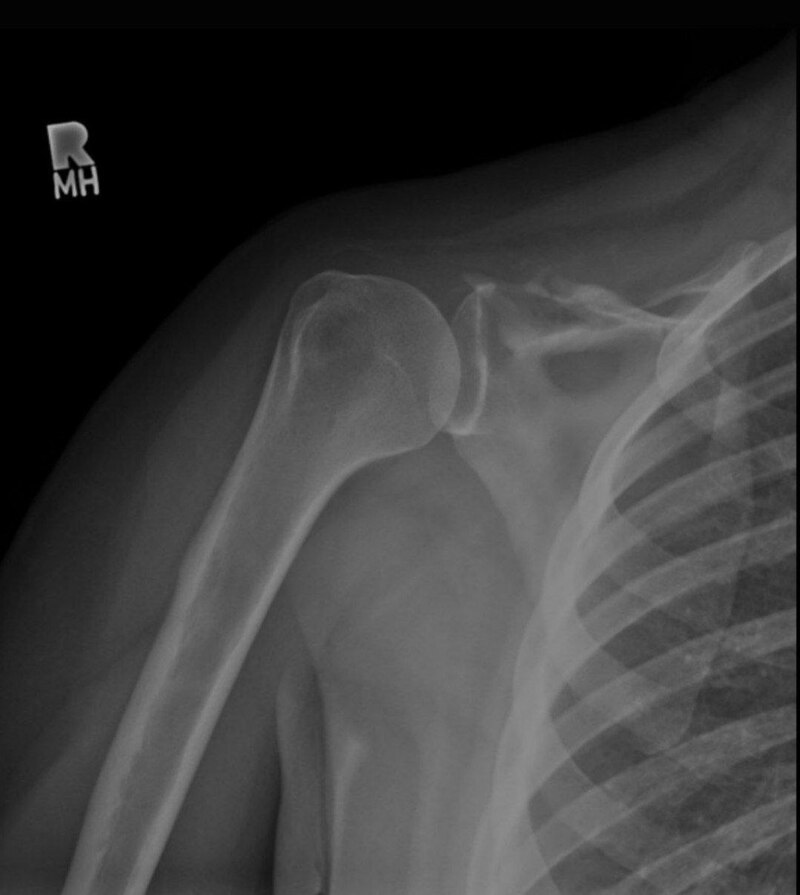

هذا المرض اضطراب نادر جداً وغير مفهوم الأسباب بشكل كامل ، راح يصير نمو غير طبيعي للأوعية اللمفاوية أو الدموية داخل العظمة بالتالي راح يصير تدمير بالنسيج العظمي ويصير امتصاص تدريجي، بشكل اوضح عدنا عظمة ال Humerus راح تذوب او تتلاشى بالصورة الأشعاعية راح يصير لونها رمادي او شفافة متبين ليش ؟ لأنو حل محلها نسيج ليفي أو أوعية دموية ، مراح يصير تجديد بالحالات الطبيعية الجسم يقوم ببناء عظم جديد مكان القديم لكن بهذا المرض الجسم ما راح يبني راح يكتفي بالهدم تشخيصة يكون صعب نكتشفة صدفة او كسر بسيط ما يلتئم ف نلاحظ بالأشعة أن جزءاً من العظمة اختفى ، اعراضه :

ألم مفاجئ او تورم غير مبرر يعني بدون سبب بمنطقة الكتف او Pathological Fracture تنكسر العظمة نتيجة مجهود بسيط لأن هيَ اساساً صارت فارغة من الداخل ف اكيد راح تكون هشة وكذلك يصير صعوبة بتحريك الذراع نتيجة تآكل المفصل